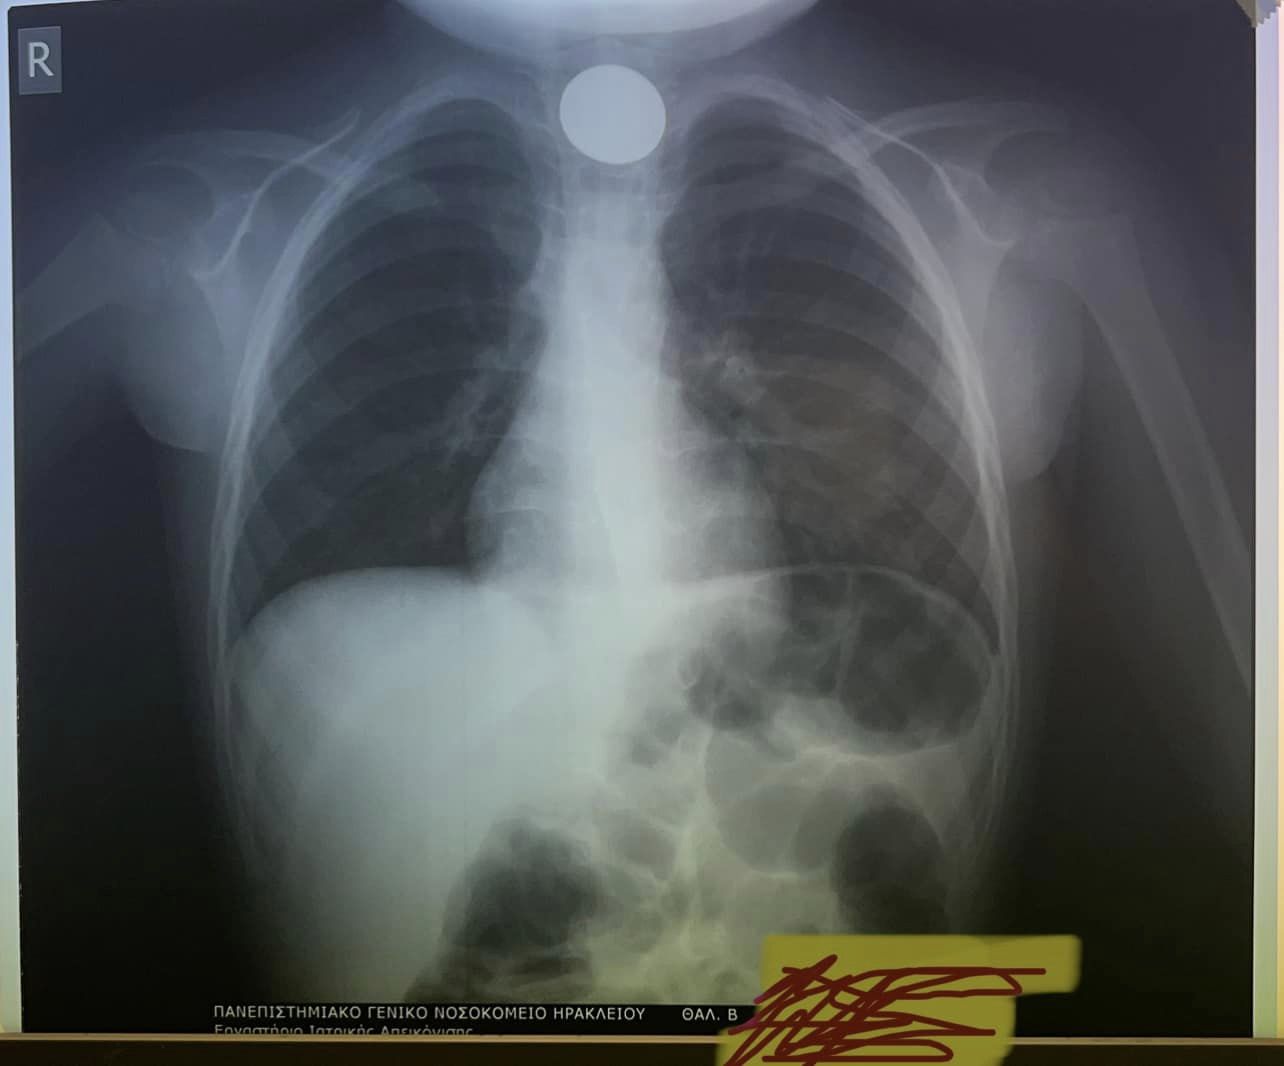

"Αποχαιρετάμε το 2023 με επείγουσα αφαίρεση σε κατάποση κέρματος σε 4χρονο. Καλή Χρονιά"!